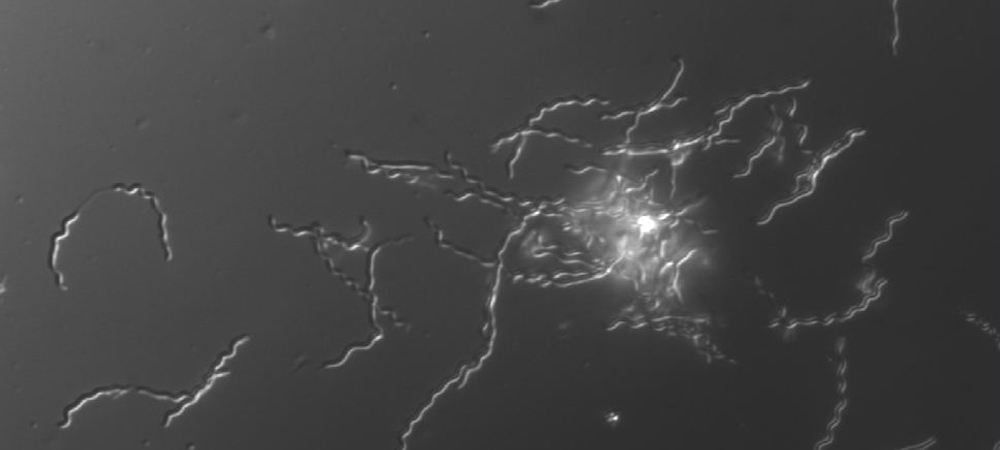

Digital dermatitis (DD), the leading cause of infectious lameness in Alberta dairy cattle, is present in 15% of cows and 94% of herds. The painful, ulcerative or proliferative lesions that characterize DD compromise animal welfare and lead to significant economic losses. Multiple species of Treponema, a pathogenic anaerobic bacterium, are consistently found in DD lesions and rarely isolated from healthy hooves. We developed qPCR assays for all major DD-associated bacteria and investigated their association with DD lesions. We are currently looking at the species present at the onset of DD lesions and in chronic lesions. Specifically, we are looking at Mycoplasma spp. in these chronic and recurring lesiosn.